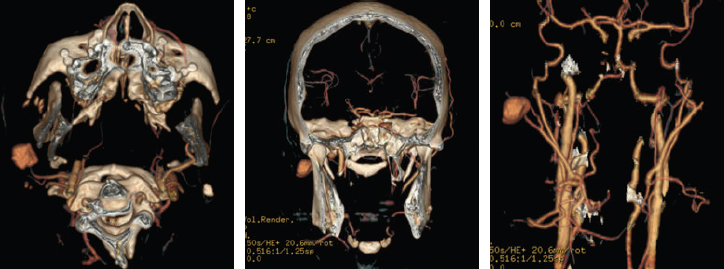

CHAPTER Orthognathic surgery involves the surgical manipulation of the elements of the facial skeleton to restore the normal anatomic and functional relationship in patients with anomalies of the dentofacial skeleton. Since its evolution from the mid-20th century with its classic procedures to the incorporation of distraction, osteogenesis has become a powerful tool in the surgeon’s armamentarium that can create dramatic changes in facial form and function that few other procedures can achieve. Achieving this desired goal involves a detailed architectural blueprint and construction details. Furthermore, it requires a close working relationship between the orthodontist and the surgeon, each manipulating their own component of the dentofacial unit in a complementary, time-specified, integrated approach. Speech and language pathologists and psychologists play an important role in guiding the treatment planning. As an elective procedure, orthognathic surgery places significant demands on patients and their families—with an overall length of treatment that spans years—in the form of financial resources and a multitude of appointments that require time off from employment and educational activities beyond the brief period of surgery and its immediate recovery. It is a significant commitment from the patient, caregivers, and professionals. Thus, practitioners must clearly define the surgical and dental goals and then concisely translate those goals to the patient and the family, including a discussion regarding why those goals may not be reached. The probable is what usually happens, but at this point the focus should be on the improbable, the unintended, and the unexpected. Thus understanding the unfavorable outcomes and surgical and orthodontic complications that can and do occur with maxillofacial skeletal procedures is the subject of this chapter. There is a relevant distinction between the “unfavorable” and the “complication.” An unfavorable outcome can occur without a specific complication, and not all complications lead to an unfavorable outcome. A perfectly well-executed orthognathic procedure from blueprint to construction without any complications can still lead to an unfavorable or unsatisfactory outcome. A face with a perfect occlusal and functional result may not be pleasing to either its owner or to the architects who designed it. Moreover, unlike many surgical procedures, the outcome depends not only on the surgical procedure itself, but also on a multitude of factors that exist long before the actual surgery, as well as on the ability to control variables long after the surgical procedure has taken place. Whether the desired long-term outcome is achieved in terms of occlusal function and aesthetics of the dental and facial form depends on whether the goals of each of the phases of treatment were achieved. Moreover, the success of each phase depends on the preceding phase of treatment. For example, inadequate incisor decompensation limits the amount of sagittal repositioning possible and compromises the final facial aesthetics. If mobilization of the maxilla at the time of surgery is inadequate and a less-than-ideal occlusal relation obtained, the postsurgical orthodontic phase is prolonged, and relapse toward the initial condition is likely to occur. Even when facial skeletal and dental goals are achieved, the functional goals may not be. Moreover, unintended consequences may occur in terms of velopharyngeal insufficiency, airway compromise, or oromotor function while optimizing facial appearance. Each orthognathic case has a stepwise sequence of diagnosis, dentosurgical treatment planning, presurgical orthodontic preparation, surgery, postsurgical orthodontic detailing, and retention. Thus, unlike many of the surgical procedures, the scale of time is not measured in weeks to months; rather, it is measured in years. The surgical component must be taken within the context of the overall treatment from diagnosis to retention. Within this lengthy time frame of a complex choreography between orthodontist and surgeon, errors occur and accumulate. The list of errors that can lead to unfavorable outcomes and complications is extensive and is well reviewed in the existing literature.1–5 A meaningful way to discuss these is to consider what can go wrong with each phase of treatment (see the Summary Box). Unfavorable outcomes occur primarily because of poor communication between the surgeon and the orthodontist and the patient6,7 (Fig. 43.1). For the vast majority, patients are referred to the surgeon by the orthodontist, whose goal is primarily to achieve occlusion that cannot be achieved without the aid of the surgeon. The surgeon assesses the patient from the perspective of optimizing the aesthetic goals of the soft tissue draping the skeletal framework within the context of achieving the orthodontist’s expected occlusion (Fig. 43.2). Each must understand the other’s objective and abilities to achieve those goals within any limitations or compromises that may occur when reaching common surgical and occlusal goals. Moreover, anatomic dentosurgical goals may negatively affect functional goals. An example is a patient with a severe class III cleft in whom a maxillary advancement procedure may put the patient at risk for velopharyngeal incompetence (VPI) while improving the anterior dental relationship, the aesthetic appearance, and speech articulation. A mandibular setback procedure used to minimize VPI may put the patient at risk for obstructive sleep apnea and a less-than-ideal facial appearance. Thus the goals of the speech and language pathologist and sleep medicine specialist may come into play. In many cleft patients, the lateral incisor is not present, and incorporating the need for either prosthodontic consideration or segmental closure with a canine-to-lateral substitution needs to be addressed from the beginning. It is more than simply filling a dental gap, because each approach will have a different outcome in perioral aesthetics of the arch form and smile. In a patient with a class II cleft in whom significant mandibular advancement would improve both aesthetic appearance and airway, the surgeon’s goal may be limited by insufficient dental decompensation that could have been achieved with mandibular first molar extractions and retraction of the anterior dentition. A bimaxillary advancement procedure could surgically compensate for improving the airway, but at the expense of the facial aesthetics. Summary Box Causes of Complications and Unfavorable Outcomes Errors in Diagnosis and Treatment Planning • Unrealistic expectations • Lack of understanding of the complexity of the procedure • Lack of teamwork between the orthodontist and the surgeon • Failure of including speech, psychology, and sleep medicine • Wrong diagnosis • Errors in diagnostic setup Errors in Preoperative Orthodontic Management • Inappropriate timing of intervention • Inadequate orthodontic setup • Insufficient decompensation • Inadequate transverse width coordination • Inadequate root divergence for segmentation • Inappropriate extraction versus nonextraction Complications in Operative Phase of Management • Errors in surgical planning • Intraoperative complications (see Box 43-1) Errors in Postoperative Orthodontic Management • Insufficient coordination of the dental arches • Inadequate postoperative posterior buccal-lingual torque • Failure of retention Unsatisfactory Outcome • Velopharyngeal insufficiency • Issues related to hardware • Chronic maxillary sinusitis • Osteotomy nonunion • Late malocclusion and relapse • Unsatisfactory facial appearance • Unacceptable nasal appearance and breathing • Unsatisfactory smile and perioral aesthetics • Issues related to temporomandibular joint Fig. 43.2 This patient was referred “ready for jaw surgery.” The patient expressed concerns to the surgeon at the initial consultation regarding the perioral aesthetics of protuberant lips. The maxillary incisors were excessively flared by the routine sequence of orthodontic arch wires. Maxillary advancement surgery would worsen the appearance, whereas mandibular setback would not alter the upper lip. However, there was no communication by the surgeon at the initial planning stage. The option of first bicuspid extraction and anterior segmental repositioning would have achieved the occlusal goal and the patient’s aesthetic goals. The outcome was compromised by a lack of communication and understanding what each can achieve. A mandibular setback was offered to achieve occlusion but at the risk of an unfavorable ramal osteotomy and poor fixation, because the third molars would have been ideally extracted 6 months before the bilateral sagittal split osteotomy procedure. From the patient’s perspective, the options available are bewildering, and the potential to negatively affect the facial appearance and function is daunting. Even when the professionals feel that the ideal occlusion and facial appearance are achieved, the patient may be unhappy with the appearance despite the often dramatic improvement in appearance. Incorporating the change within the patient’s psyche can be difficult. I have had adolescents who were not sufficiently prepared for the physical changes to return to school and older patients in the third decade and beyond who equally were unhappy with what I considered an improved appearance. In two decades of experience, I have found the involvement of a psychologist from the initial discussion for orthognathic surgery to be critical. This is especially true in adolescence, when many patients are defining their identity and facing stress at home and social and academic stress at school. Our psychologists have uncovered suicidal ideations, drug and alcohol abuse, sexual orientation, and pregnancy unknown to the orthodontist, the surgeon, and the parents. Such sensitive issues within the context of dentofacial surgery, if missed, can lead to disastrous outcomes. Understanding the patient’s motivation for surgery is an important factor in a successful outcome.8,9 Taking the time to communicate the complexity of the orthodontic and surgical treatment and their impact is critical to optimizing the outcome with the end result of a satisfied patient comfortable with his or her new appearance and functional bite. The patient must have an understanding of limitations and compromises that may occur. Orthognathic surgery, whether needed for cleft or craniofacial conditions or for the more common developmental deformities, should be approached as a multidisciplinary team perspective and not just involve the orthodontist and surgeon independently driving the entire treatment plan. In addition, we have found it enormously beneficial to establish a dedicated “jaw” clinic, in which the vast majority of the patients are at various stages of jaw treatment. We have found that patients and their families become more comfortable with surgery after talking to each other in such settings. The supportive group that naturally develops is a powerful tool in communication that leads to a successful outcome. The wrong diagnosis will lead to the wrong surgery and to an unsatisfactory or unfavorable outcome. A classic example is patients who feel that their mandible is “too prognathic.” They come to the surgeon wanting to have their mandible and chin brought back. In a true profile view this may at first seem acceptable. But many of these patients will have subtle signs of midfacial deficiency that would be missed with this treatment plan and would be better served by a maxillary advancement procedure as the primary procedure to optimize their aesthetic appearance. The surgeon and the orthodontist should note the lack of dental display, the perialar deficiency, the acute nasolabial angle, the deficient columellar projection, and the convexity of the face that may extend to the zygomatic region. These can only be assessed when seeing the patient clinically in three dimensions and are often missed in the standard orthodontic two-dimensional photographs that often accompany the patient at the time of referral. Of all the images, the three-quarter oblique view often best reveals the midfacial deficiency that is commonly missed in the true lateral profile view. Another relevant example is when patients come to the surgeon initially for a recessed chin wanting a chin augmentation. Without assessing the dental occlusion, the aesthetic outcome from symphyseal surgery, whether osseous or alloplastic, may be unsatisfactory. If the patient has a significant class II dental relation indicating a mandibular body deficiency, then a “camouflage” genioplasty may result in an unnaturally deep labial mental sulcus if advanced to the desired projection. Such patients would benefit from an orthodontic assessment and consideration for a mandibular body advancement and an osseous genioplasty. There also may be symptoms of obstructive sleep apnea (OSA) that can be missed if the surgeon focuses only on the chin projection without considering occlusion and retroglossal airway space. The origin of the occlusal discrepancy can unfavorably influence the outcome of surgery if the underlying cause is not addressed or taken into account in the treatment planning. Concerns of relapse, vascularity, and secondary impact on velopharyngeal dysfunction are greater for patients with facial clefts requiring maxillary advancement than for patients with developmental dentofacial skeletal deformities. Patients with developmental dentofacial deformities who present for correction of an anterior open bite deformity are at an increased risk of relapse if the underlying cause of tongue thrust is not managed. Patients with condylar hyperplasia who present with prognathic mandibular asymmetry and occlusal class III cross-bite may exhibit continued asymmetric growth with a resulting recurrence of the condition if the underlying pathology remains active. Patients who undergo mandibular advancement surgery may progressively relapse with time as a result of underlying temporomandibular joint (TMJ) pathology, such as juvenile rheumatoid arthritis or idiopathic progressive condylar resorption unrecognized before surgery. Optimizing the outcome demands an understanding of the underlying causes of the dentofacial skeletal deformity whether of congenital, developmental, or traumatic origin, each of which influence the outcome differently despite the similarity in surgical procedure and desired goals. Accurate records are needed for diagnosis and to detail the orthodontic and surgical treatment planning at two critical time points: (1) at the beginning before there is any intervention, a diagnostic setup, and (2) at the time of surgical planning weeks before the procedure, a surgical setup. Too often the surgeon is brought into the picture in the middle of orthodontic treatment, and the only involvement is at the time of the surgical setup (the model surgery), resulting in compromises that could have been addressed at the time of the diagnostic setup. At both junctures, the setup must be accurate to reflect the patient’s initial dentoskeletal anatomy and allow the team to predictably plan the optimal end point. Historically, the complexity of the three-dimensional facial architecture was reduced to a series of two-dimensional records captioning the soft tissue envelope using photography and the underlying skeletal framework with plain radiographs in multiple orthogonal planes. The dental models were the only component that was recorded in three dimensions, and they required using a face-bow for positioning in the three-dimensional space. However, developing an accurate three-dimensional composite model of a patient’s condition by registering each of the two-dimensional orthogonal radiographic planes (lateral cephalometric and frontal cephalometric) and the two-dimensional photographs (frontal and profile views) with the mounted three-dimensional dental models had its own difficulties. Registration errors would build with each step, and any simulation of the treatment planning (sectioning and repositioning the plaster-mounted models) would lead to uncertainty about the accuracy of transferring the surgical plan to the operating room.10,11 Beyond the laboratory technical errors is the fundamental difficulty in the consistency of the head position and in the difficulty in accurate face-bow mounting in the cases of asymmetry that would involve the ear, the skull base, the orbits, and dual-plane maxillary–mandibular asymmetry. Traditional model surgery worked well in the routine developmental dentofacial skeletal cases, in which the vast majority of patients’ problems could be captured within the two-dimensional sagittal plane. However, when the problem extends to the third dimension, where yaw, roll, and pitch of the maxilla and the mandible play a role, it becomes less reliable, and successful orthognathic surgery becomes more of an art than a series of well-defined steps to a desired outcome. In cases of asymmetry, the roll and the pitch are easier to correct, but the yaw is missed because of the inability to accurately visualize the problem in the transverse plane. Today, surgical-orthodontic management has become increasingly reliable with the ability to visualize structures using three-dimensional radiologic cone beam computed tomography (CBCT) and software that allows the surgeon to simulate surgery with three-dimensional movement of the skeletal components.12,13 The next generation of maxillofacial surgeons will be fully immersed in three-dimensional technology, allowing a virtual orthodontic and surgical simulation that is specific to the patient’s anatomy.14–16 Although the technical execution of the planning and model surgery would be expected to improve with elimination of registration errors, it is important to remember Obwegeser’s Principle Number 35,17 “The computer can show you what you can achieve with your planning but cannot plan for you.” Knowing where to position the maxillary–mandibular skeletal bases and the dental arches relative to the desired soft tissue envelope is dependent on the surgeon’s and orthodontist’s eye, experience, and intuition, which cannot be replaced by a computer.17 Accurate clinical and radiographic diagnostic assessment of the facial appearance and the underlying dentofacial skeletal structure will point to the structural regions that are malpositioned and malsized relative to the skull base and to each other. The problem is not in determining what is wrong, but determining where the skeletal elements and consequently the dental component should be positioned.18,19 The surgeon and orthodontist will each have their own notion of the normative facial structure, and the patient will likely have a differing internally biased expectation of the desired facial appearance. Orthodontists often rely on normative cephalometric numbers, which is understandable because cephalometric analysis is historically rooted in the profession. Patients typically base their expectations on what they see in the media of models and actors. The surgeon must balance the patient’s expectations with what can be realistically achieved by defining the new skeletal framework and the occlusion simultaneously. It is important to understand that no patient wishes to look “average” and that the use of normative cephalometric data should only be used as a guide.20,21 As an illustration, although a sella–nasion–A point (SNA) angle of 82 degrees is considered an average, it may be unattractive compared with an SNA angle of 84 degrees or more if this would result in an attractive facial appearance with fullness and better support of the midfacial soft tissue envelope. An SNA angle greater than 82 degrees may also have a significant favorable effect on the patient’s smile. Buccal corridors that are empty before the advancement can be better filled with the dentition from canine to canine for a more attractive, fuller smile. A lesser advancement would result in a less full smile. Because the dentition can be adjusted orthodontically and the dental arch as a unit surgically, the final desired maxillary and mandibular incisor inclinations and thus the orthodontist and the surgeon determine the smile aesthetics to be achieved by the treatment. Comparing for the patient the difference between the patient and his or her siblings and parents serves as a guide toward what goals can realistically be achieved. Once the final skeletal position is determined relative to the skull base, the surgeon and the orthodontist need to work backward. The orthodontist needs to determine what to do with the teeth to allow the surgeon to achieve the final skeletal position in the construction of the desired face. A classic example is in cleft patients who present with a class III dentofacial skeletal relationship, in which the skeletal deficiency is more than the dental discrepancy. The surgeon would like to significantly advance the midface, but the skeletal advancement is limited by the minimal discrepancy at the occlusal level (insufficient negative overjet). The outcome would be less than ideal without orthodontically increasing the negative overjet. If the orthodontic preparation was not ideal, alloplastic implants may be needed as a compromise. Similarly, for class II patients who would benefit from significant mandibular body advancement, the occlusal relationship may be insufficient to allow for the desired advancement, and the projection of the facial plane must be made up by an osseous genioplasty. There must be adequate dental decompensation to make the occlusal relationship worse to achieve the desired skeletal movement to optimize a favorable outcome. Although the treatment planning options are well established to optimize outcome in the developmental dentofacial skeletal cases, for congenital conditions ranging from minor facial clefts to syndromic conditions as Goldenhar and Treacher Collins, the path to the final goals is not as clear. Classic approaches are challenged by severe tissue deficiency at multiple tissue planes and severely abnormal architecture, so simple rearrangement of the existing skeletal elements cannot be achieved in a stable manner without bone grafts. Unlike developmental cases, for which surgical intervention primarily takes place at skeletal maturity, the need to intervene in the actively developing immature skeleton is motivated by functional concerns and the need to limit compensatory or progressive distortion of the anatomy. Distraction osteogenesis allows the surgeon to use the biologic machinery to lengthen bone and expand the hypoplastic surrounding soft tissue matrix: muscle, nerve, and integument. It is in such cases that the surgeon enlists the aid of the orthodontist to support the functional and reconstructive goals with the understanding that the occlusal outcome may initially be less than ideal with distraction alone. Solving the three-dimensional nature of the problem is hindered by the limited ability to control the vector of the distraction process because of the simplicity of the mechanical devices. It is generally unidirectional and at best bidirectional. Thus, in the end, classic orthognathic procedures are likely needed to fully control the three-dimensional nature to optimize the outcome. The surgeon must therefore communicate to the patient and the family that a distraction may need to be multistaged to address the different vectors through different periods of growth and development, and that classic orthognathic surgery is commonly needed at skeletal maturity to allow the surgeon and the orthodontist full three-dimensional control over the reconstruction. Expectations must be managed. Skeletal surgery is “carpentry,” and that carpentry does not restore normal growth and development in these children. It puts the bones where they should be, but in a growing child the arrangement is not likely to remain ideal, either because of relapse or lack of growth. Relapse can be limited by distraction, but may not restore growth because of the underlying pathology. Optimizing the outcome of orthognathic surgery for cleft patients begins long before skeletal maturity (Fig. 43.3). In my practice, it begins in early adolescence at age 12 to 14 years, when it is important that both the surgeon and the orthodontist assess the cleft patient and begin the discussion with the family of the possible need for skeletal correction and occlusion depending on mandibular growth and on the maxillary deficiency that is common at this age. Early discussion with the family, monitoring growth, and a close working relationship with the orthodontist will alleviate some of the difficulties that may be encountered in late adolescence if treatment planning is delayed. The surgeon and the orthodontist must address several considerations in early adolescence: 1. Status of the alveolar bone graft 2. Need for cleft orthognathic surgery 3. Management of the typically missing lateral incisor Ideally patients have undergone phase I orthodontics that would involve transpalatal expansion, initial alignment of the dentition, and iliac bone grafting of the primary alveolar cleft in early mixed dentition. If this has not been addressed, it should be done before initiating phase II orthodontics when the patient is in permanent dentition. This is needed to support the dentition adjacent to the cleft margin, allow canine eruption and orthodontic movement across the cleft site, and improve gingival-mucosal vascularity. In many cleft patients, the lateral incisor is congenitally missing, has been extracted because of inadequate bone support, or is lost because of dental caries. A decision must be made with the family, the orthodontist, and the restorative prosthodontist whether to maintain the dental space for an implant-retained dental prosthesis or a bridge versus segmental maxillary osteotomy and closure of the dental space by moving the canine into the lateral incisor position. If a canine substitution is planned by advancing the lesser alveolar segment, then the cleft site may not need to be grafted before segmentation unless bone is needed to support the central incisor and canine root. In many cleft patients, there is a transverse width discrepancy even after phase I orthodontics that is significant in adolescents at the time of consideration for phase II final orthodontic-surgical management. Although a segmental Le Fort I osteotomy can correct a residual transverse width discrepancy, my experience is that immediate surgical expansion at the time of surgery can be accomplished but difficult to maintain despite orthodontic retention because of the relapsing forces of an inelastic scarred palatal mucosa. Our preference is to correct the transverse width with slow expansion using a transpalatal expander and when needed unilateral or bilateral maxillary osteotomy (surgically assisted palatal expansion) before formally correcting the sagittal and vertical skeletal discrepancies. Thus my goals for cleft patients include the following: 1. Convert a multisegmented cleft alveolus to a noncleft single dental maxillary alveolar arch. 2. Address the missing lateral incisor early in the planning in terms of substitution versus replacement. 3. Correct the transverse width discrepancy before sagittal and vertical advancement (with surgically assisted palatal expansion if needed). 4. Optimize the facial skeletal aesthetics by maximal dental decompensation with a treatment plan established in early adolescence well before skeletal maturity. There are pitfalls in the preparation of the dentition for orthognathic surgery that must be well understood by the orthodontist and the surgeon.6,22,23 Less-than-ideal orthodontic preparation will lead to a less-than-ideal surgical and occlusal outcome (see Fig. 43.2). In patients with skeletal discrepancies requiring orthognathic surgery, dental compensations occur as a natural biologic response to optimize occlusion in the face of maxillary–mandibular discrepancy. These dental compensations occur in all three planes: anterior-posterior, transverse, and vertical. A surgeon whose goal is to optimize the aesthetic skeletal outcome and an orthodontist who seeks to achieve maximal coordination (intercuspal relationship) of the dental arches must agree on the extent to which the teeth must be decompensated before skeletal surgery. Failure to communicate at the outset the goals from each perspective and the compromises that must be made will result in a disappointing outcome. The goal is determine the ideal skeletal projection and then determine how to handle the dentition to achieve the desired skeletal result. Fig. 43.3 This patient had been undergoing orthodontic treatment for more than 2 years when he was referred to a surgeon at age 18 years, 3 months before his high school graduation. The patient and his parents were anxious for the “final” surgery shortly after graduation because he was planning to attend college in another city. However, the cleft alveolus was never reconstructed, and there was a missing lateral incisor. Ideally one of the options discussed with the family would have included cleft alveolar bone grafting for stabilization of the dental arch with preservation of space 10 for subsequent osseointegrated implants versus a segmental Le Fort I closure of the dental space with a canine substitution for the missing lateral incisor. Because the patient would need correction of the mandibular asymmetry, the impacted mandibular third molars would have been extracted well before the orthognathic surgery to minimize unfavorable osteotomies. In addition, the patient had velopharyngeal insufficiency that would likely worsen with the maxillary advancement. Thus the critical need for surgery for the velopharyngeal incompetence limited by the mid-August start of school made it nearly impossible to proceed with the cleft orthognathic surgery as the family had planned. The cleft nasal and lip revision surgery needed to be addressed after the orthognathic surgery, but the patient was hoping to have had this improved before he started college. This case illustrates the importance of thoughtful treatment planning at the beginning of care before initiating orthodontic treatment. In patients with a class III skeletal pattern, the maxillary incisors are typically flared and the mandibular incisors are upright or even retroclined. Failure to appropriately decompensate will result in an insufficient negative overjet and in turn will result in inadequate maxillary advancement and/or inadequate mandibular setback to optimize the aesthetic outcome. The surgical goals are thus compromised. Additionally, inadequate decompensation may result in inability to achieve a class I buccal segment limited by the angulation of the anterior dentition. The occlusal goals are thus compromised. When a significant negative overjet is needed from a skeletal perspective, the anterior dentition from canine to canine can be righted and retracted by extracting either the first or second premolars to make room in the dental arch. Which set of premolars to extract depends on the amount of crowding and the amount of retraction needed. In the lower arch, decompensating the lingual inclined or righted mandibular incisors allows for further increase in the negative overjet. With severe anterior mandibular dental crowding, extraction of a single central incisor can be an option. Leaving the patient with three central incisors can be an acceptable compromise, because the lower dental midline is not visible until late in life. Moreover, decompensating by proclining the lower anterior dentition improves the support and aesthetic projection of the lower lip to create a desirable labial-mental sulcus. In patients with a class II skeletal pattern, the opposite occurs. The mandibular incisors are flared (proclined) and the maxillary incisors are righted. In patients with severe convexity who would benefit from maximal mandibular advancement from an aesthetic perspective and functionally from an airway perspective, the orthodontic goal would be to maximally decompensate the dentition to increase the positive overjet. Failure to maximally decompensate the anterior dentition limits the surgeon’s ability to advance the mandible and limits the orthodontist’s ability to achieve class I buccal segments postsurgically. Maximal decompensation may require extraction of either the first or second mandibular premolars to allow retraction of the anterior dentition into the extraction spaces. Additionally, proclining the maxillary incisors adds additional overjet to the mandibular decompensation and improves the upper lip support. As with the anterior-posterior compensations for skeletal discrepancies, there is transverse compensation that needs to be addressed in the presurgical phase to prevent postsurgical cross-bite and lingual-buccal inclinations. This is best assessed by hand articulating dental study models in a class I canine relationship. The decision that the orthodontist and the surgeon must make is whether the transverse width discrepancy can best be addressed by orthodontically based expansion alone, surgically assisted orthodontic expansion, or multisegmental surgical maxillary expansion. When the intercanine width is narrow, a two-segment maxillary expansion is an option to correct the width discrepancy. If the intercanine width is appropriate but there is a posterior buccal cross-bite, a three-segment maxillary expansion can be considered. Thus there must be sufficient interdental spacing and root divergence to allow the surgeon to safely accomplish the interdental osteotomy to minimize compromising adjacent tooth vitality. For patients who present with apertognathia, a Le Fort I osteotomy with posterior maxillary impaction will allow skeletal closure of the open bite. In such patients the curve of Spee may be excessive, and prior leveling of the curve should be done with care. Mandibular incisors will typically be overerupted and decompensated orthodontically. However, orthodontic leveling of the curve of Spee in the maxillary dental arch may create a risk for postoperative relapse and recurrence of the open bite, especially when the vertical leveling must exceed 2 mm. Excessive maxillary incisor extrusion before a single segment Le Fort I surgery is likely at risk for relapse of an open bite of dental origin. In such cases multisegmental orthodontic alignment and osteotomies are a more stable treatment choice. Operative complications of orthognathic and maxillofacial distraction surgery can be categorized by the surgical technique (Box 43.1). However, because the various maxillofacial surgical procedures are interrelated and are commonly performed in combination, operative complications are best discussed in the following broad categories. Intraoperative airway control is critical; nasoendotracheal intubation is necessary for surgical treatment of occlusion with maxillary–mandibular fixation. Nasal intubation can be difficult in patients with facial clefts who have previously undergone a pharyngeal flap procedure. Intubation can be accomplished with fiberoptic guidance and/or exchange over a stent after oral intubation. Occasionally, nasal intubation is not possible and, although less preferable, the procedure can be performed in these cases with orotracheal intubation and with the oral tube positioned retromolar at the time of maxillary–mandibular fixation. During the posterior aspect of the Le Fort I osteotomy, the nasotracheal tube is particularly at risk at the times of septal–vomer dysjunction and with the osteotomy of the lateral nasal wall on the side of the tube. The tube itself or the access to the balloon cuff can be lacerated or transected by the osteotome or by the reciprocating saw.24,25 In the case of complete transection, immediate air leak or loss of air exchange is evident by blood within the endotracheal tube. To prevent endotracheal tube injury, I first perform the septal dysjunction with a guarded osteotome; this facilitates placement of the reciprocating saw within the nasal piriform, because the septum and nasotracheal tube are deflected to the opposite side, decreasing the risk of injury to the tube. The maxillary osteotomy is made with a reciprocating saw and should be directed from medial to lateral, away from the nasotracheal tube (Fig. 43.4). If injury to the nasoendotracheal tube occurs, exchange of the tube is easier before the maxillary osteotomy is initiated.25 In the case of laceration of the tube or the balloon and a resulting mild air leak when tube exchange would be difficult, posterior oropharyngeal packing may be beneficial in controlling the air loss. There are several reasons for increased airway resistance after completion of the maxillary–mandibular surgery. Intermaxillary fixation increases airway resistance, reducing peak air flow, and patients who have undergone a Le Fort I procedure in addition will necessarily have some degree of nasal airway obstruction.26 For these reasons, many prefer no maxillary–mandibular fixation or only guiding elastics during the immediate recovery period. Coughing or straining with agitation can cause a fracture or an avulsion of the internal fixation hardware. Avoiding maxillary–mandibular fixation may also reduce the risk of this complication. I prefer not to use any maxillary–mandibular fixation during the immediate recovery phase for patient comfort until the first postoperative appointment, 1 to 2 weeks after surgery. Any preexisting coagulopathy should be determined through a history and physical examination. Patients should be specifically asked about a history of excessive bleeding after minor injuries or bleeding after previous procedures such as third molar extractions. In addition, a careful medication history should be taken, with particular attention to the use of medications such as aspirin, other medications with anticoagulant properties, and herbal or nonformulary medications whose composition might not be clear. These should be stopped long before surgery. Maxillary Procedures (Le Fort I) • Avascular necrosis • Dental injury (segmental) • Fixation failure (plates, screws, and distraction devices) • Gingival recession (segmental) • Hemorrhage • Infection • Injury to the internal maxillary artery • Injury to Stensen’s duct • Lacrimal duct injury • Malocclusion or relapse • Maxillary sinusitis • Nasal septal deviation or perforation • Traction injury of the infraorbital nerve • Transection of the descending palatine neurovascular (inevitable) • Transection of nasopalatine artery • Unanticipated fractures • Vascular injuries (arteriovascular fistula, aneurysm) • Velopharyngeal insufficiency • Vision (blindness) Mandibular Procedures (Bilateral Sagittal Split Osteotomy, Intraoral Vertical Ramus Osteotomy) • Avascular necrosis • Condylar resorption • Fixation failure (plates, screws, and distraction devices) • Hemorrhage • Infection • Traction injury of the inferior alveolar neurovascular bundle • Traction injury of the lingual nerve • Transection of the inferior alveolar neurovascular bundle • Malocclusion or relapse • Malpositioned proximal ramus • Unanticipated fractures • Vascular injuries (arteriovenous fistula, aneurysm) Genioplasty • Gingival recession • Fixation failure (plates and screws) • Mental nerve injury • Mandibular border contour deformity Fig. 43.4 Endotracheal tube position after nasotracheal intubation. The balloon tubing and/or the endotracheal tube can be lacerated. The endotracheal tube may be injured during osteotomy through the medial buttress. Directing the saw from medial to lateral will minimize the risk of transecting the endotracheal tube. Separating the septum first will increase the intranasal space before the maxillary osteotomy and facilitate placing the saw within the nasal cavity. The use of local anesthetic with a vasoconstrictor and controlled hypotensive anesthesia significantly reduces generalized bleeding and the need for blood transfusion while greatly improving visualization of the operative field.27,28 One study demonstrated controlled operative hypotension reduced blood loss by approximately 44%.29 Significant hemorrhage is uncommon, but it is more likely with maxillary osteotomies.3,29 With maxillary osteotomy, the vessels at risk include the greater palatine vessels, the maxillary artery, and the pterygoid plexus.30,31 Bleeding from the descending palatine vessels occurs when the posterior aspect of the lateral nasal wall osteotomy is made and, in most circumstances, spontaneously stops as it is retracted into the bony canal. However, in such circumstances it is important to carefully visualize the site of the descending palatine vessels and coagulate with a flat-tip monopolar cautery pressed against the bone. When bleeding persists and the vessels can be visualized, it is easily controlled by vascular clips or bipolar electrocautery once the maxilla is downfractured. Such lacerations can be avoided by stopping the osteotomy at the palatine bone and keeping it as low as possible near the tuberosity as the maxilla is slowly downfractured and the vessels identified. The descending palatine artery may also be compromised during pterygomaxillary separation and may require pterygopalatine fossa packing. Because the separation of the pterygopalatine plate with an osteotome is not directly visualized, placement of the osteotome at its inferior aspect by palpation is critical to avoid injury to the vessels within the pterygopalatine fossa. The margin of safety is approximately 10 mm.32 Hemorrhage, when it does occur, can be rapid and is best controlled by dense packing of the fossa with cottonoid sponges soaked in an epinephrine solution. In most cases, bleeding, although significant, is easily controlled by local measures. When bleeding cannot be controlled by local measures, the operative site should be packed with cotton, the maxilla returned to its original position for compression and plated, and the patient transferred to interventional radiology for vascular control via embolization. Carotid ligation is a means of last resort if interventional radiology is unavailable and the bleeding cannot be controlled by these maneuvers. While significant hemorrhage with mandibular osteotomies (bilateral sagittal split osteotomy [BSSO], intraoral vertical ramus osteotomy [IVO]) is uncommon, the vessels at risk include the inferior alveolar, the maxillary, and the facial arteries; the retromandibular vein; and the pterygoid venous plexus.33–36 Careful subperiosteal dissection, retraction of soft tissues, and lateral splitting protected by appropriate retractors help prevent vascular injuries in most patients. During the exposure of the medial surface of the ramus, vascular injury to the inferior alveolar neurovascular bundle where it enters the mandible may occur with inadvertent supraperiosteal dissection. In dissecting the medial ramus, it is helpful to start the dissection anterior to posterior and superior to inferior. As the exposure continues inferiorly from the sigmoid notch, the inferior neuromuscular bundles are reflected and protected by the elevator and/or a medial ramus retractor. If bleeding occurs, epinephrine-soaked cotton can be used temporarily to pack the medial ramus to control the bleeding; however, the split may need to be completed before bleeding from the posterior ramal border can be controlled. At the time of splitting of the mandibular ramus, the inferior alveolar neuromuscular bundles are at risk. Using a wedge-shaped osteotome and directing the split along the lateral cortex can minimize the risk of injury, but the risk cannot be fully eliminated because the bundles course within a narrow width of the ramus. Bleeding along the course of the artery resulting from injury at the time of the split usually stops spontaneously. If it does not, the artery can be dissected away from the inferior alveolar nerve and carefully ligated. Cauterization poses a risk to the nerve and should be avoided. In addition, at the time of the split, the inferior and posterior border must be protected with a channel retractor to minimize risk to the facial artery and retromandibular vasculature. For persistent bleeding, as may occur when the masseteric or the facial artery is injured during mandibular osteotomy, temporary packing with pressure is sometimes helpful. Significant facial artery injuries require isolation of the vessel and its ligation.37 Even with intraoperative control, patients will present in the immediate postoperative period with bleeding as they become normotensive. Any expanding hematoma should of course be reexplored immediately. In most cases the descending palatine artery is the primary source of postoperative bleeding missed intraoperatively.38 It is preferable to allow the patient to become normotensive after the osteotomies and downfracture to control any actively bleeding vessels. It is important to note that intraoperative vascular events that may be life-threatening may only become evident in the outpatient setting in the early recovery period weeks after the surgery (Fig. 43.5). Uncontrolled epistaxis, arteriovenous fistulae, false aneurysms, carotid cavernous fistulae, and carotid artery thrombosis after either maxillary or mandibular osteotomies have been reported as isolated rare case reports.39–42 Suspicion must be high, and computed tomography (CT) angiography and embolization are needed. Mucosal degloving, osteotomies, and repositioning of the facial skeletal elements may reduce the blood supply to the osteotomized segment significantly. This reduction in blood supply can affect both the skeletal and soft tissue elements (pulp, periodontium, and gingiva). Usually, this vascular compromise is transient without significant clinical impact on the outcome.31,43 Devitalization of the teeth, periodontal defects, and segmental bone loss have been described after segmental Le Fort I osteotomies44,45 (Fig. 43.6). These complications often have been attributed to incisions, to excessive stripping of the periosteum, to scars in the palatal mucosa (secondary to previous cleft surgery), to interdental or segmental osteotomies with loss of the attached gingiva, and to transverse expansion with an excessive stripping of the palatal mucosa. When persistent intraoperative gingival cyanosis is noted during the surgery, the surgeon may consider returning the maxilla to its original position and placement of midfacial distraction appliances at the time of the procedure. An alternative is readvancement 2 weeks after surgery when the mucosal vascularity is improved as a delayed advancement.